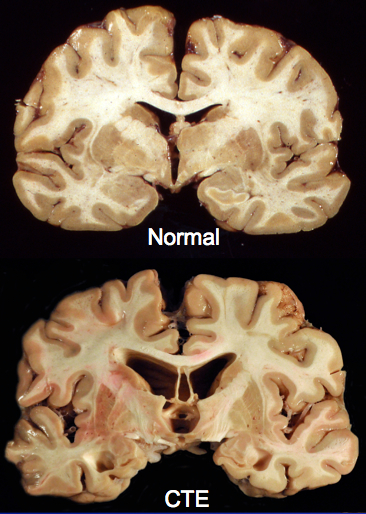

This may be of interest to some of you guys. Earlier today, I posted something about the late hockey player, Derek Boogaard, and his probable struggles with CTE. There has been some follow-up research done that shows CTE impacts athletes differently than the rest of the population. Any profession that runs the risk of head injury can leave people with this debilitating disorder, but athletes – especially football and hockey players – can be especially susceptible. From The Canadian Press:

For the study, published online Wednesday in the journal Neurology, the research team looked at the brains of 36 male athletes, aged 17 to 98, and diagnosed with CTE after death.

Most had played amateur or professional football, while the rest had played hockey or were involved in wrestling or boxing. None of the subjects had other brain diseases, such as Alzheimer’s.